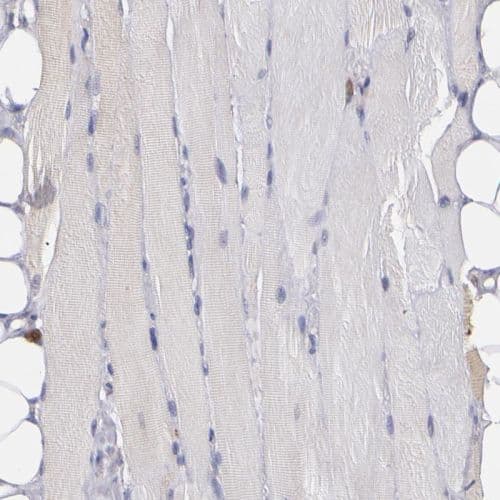

Rabbit Polyclonal COX1 / Cyclooxygenase 1 antibody. Suitable for IHC-P, WB, ICC/IF and reacts with Human samples. Cited in 1 publication. Immunogen corresponding to Recombinant Fragment Protein within Human PTGS1 aa 350-550.

Applications ICC/IF, IHC-P, WB